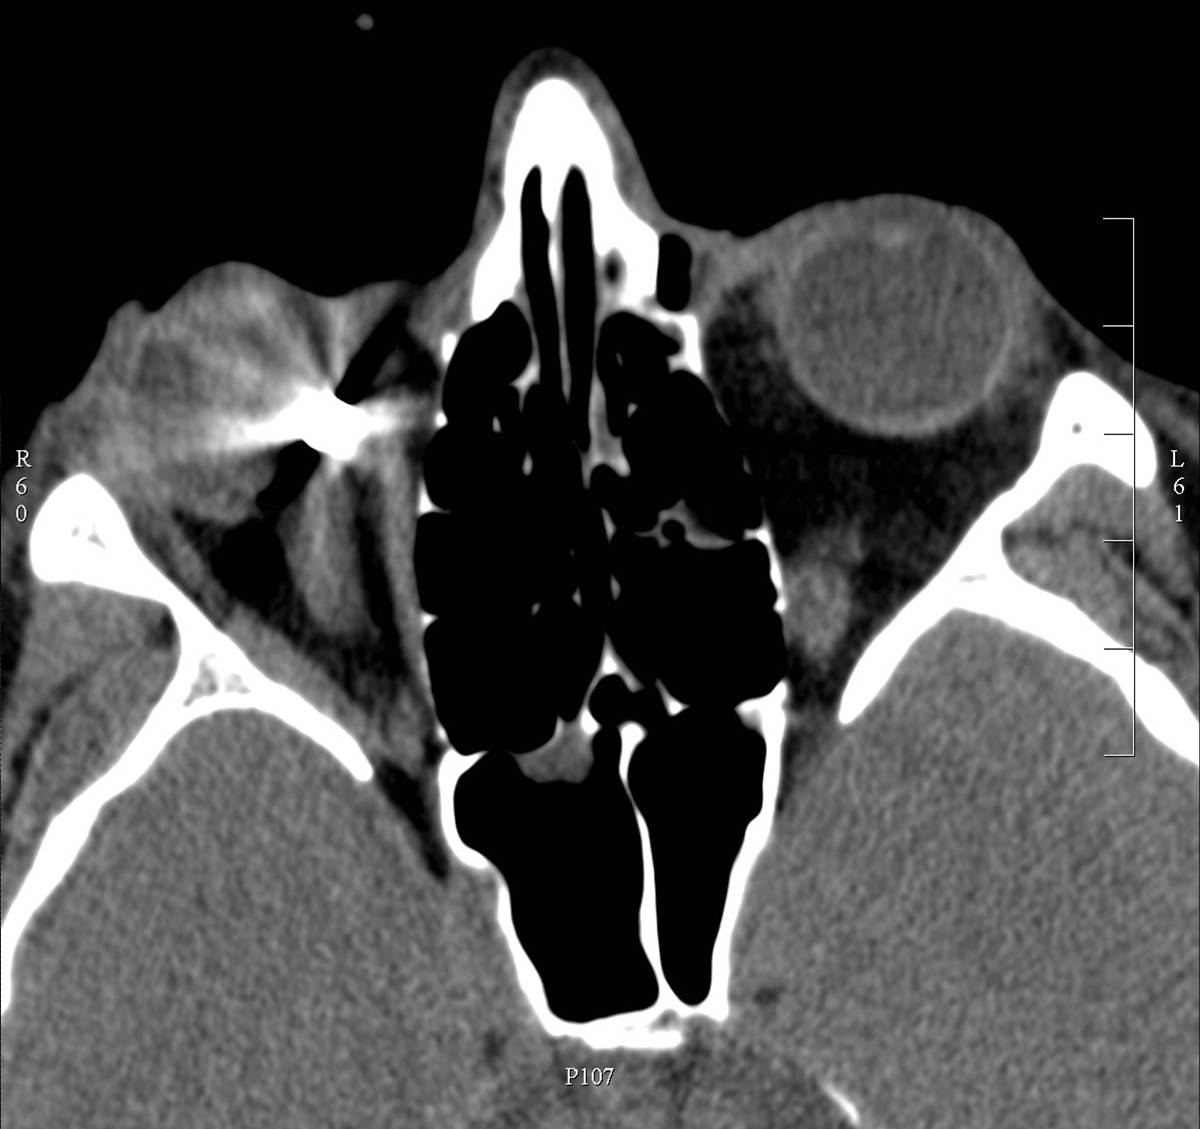

15.2.2.3. Traumas of the facial bones

They are emergencies as in part of the cases they, although, are not life threatening, can alter quality of life. Preservation of organs of vision, smell and taste sensation as well as

the integrity of facial features and mimics have an importance beyond question. The bony environment and reconstructive surgery techniques are necessitating that in this region MDCT is indicated. In the work up post-processing of the primary images can be relevant e.g. 3D reconstructions are prepared for surgical planning.

• Fractures of the facial bones are classified (Le Fort I-III. types) into separate groups based on whether only the alveolar process (dentoalveolar) is interrupted, a pyramid shaped fracture of the maxillary bone below the inferior orbital rim is seen, or the entire viscerocranium is separated from the skull base.

• The blunt hit of the orbit and the thin bony wall especially causes burst in the direction of the maxillary sinus it is called blow-out fracture. During this event part of the orbital contents protrudes into the sinus, risking entrapment between the bone layers. It can lead to eye movement dysfunction / altered vision. CT is the method of choice to diagnose fractures .(In case of a trauma we could not be certain that there is no ferromagnetic metallic object in the eye socket, that can act as a projectile during the MRI exam). Because of small, non-dislocating fractures x-ray of the orbita is not sufficient. The patient’s age and the radiation proctection of the lens should be also considered.